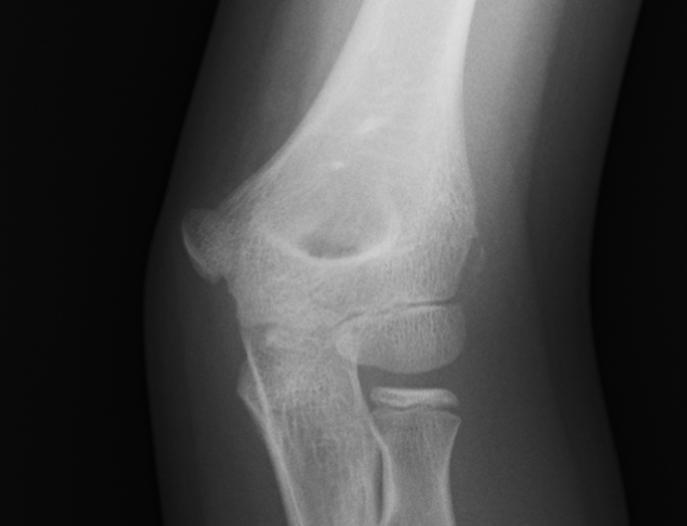

右肘外側野球肘(離断性骨軟骨炎) *画像左側が患側、右側が健側

レントゲン写真において、赤丸の中の骨が透けて見えるのが確認できると思います。反対側の青丸内は正常の骨です。野球肘は外側の痛みや画像異常が出現すると重篤となります。内側の痛みから始まり外側まで痛みが出てきた場合は手遅れとなる事が多いので注意して下さい。野球肘や野球肩は、場合によっては1年間以上投げられないという事もあります。ひどい場合は手術となってしまう事もありますので早期診断が必要不可欠です。